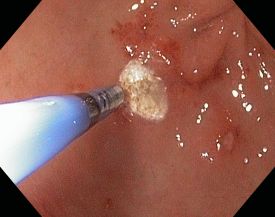

- Abtragung von Polypen im unteren Verdauungstrakt

- Mukosektomie / endoskopische Mukosaresektion (EMR) von lokalen Tumoren, erkrankter Schleimhaut und Gewebe

Bei Bedarf können außerdem über einen Instrumentierkanal im Koloskop Gewebeproben (Biopsien) entnommen werden oder therapeutische Maßnahmen, wie Entfernung vom Darmpolypen, durchgeführt werden.